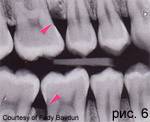

Образование пародонтальных кист происходит из десмодонтального пространства. Рассеянные в нем остатки эпителиальных клеток (по Mallessez) пролиферируют из маргинального пародонта в результате воспалительного раздражения. Пародонтальные кисты представляют собой, как правило, большие трудности для дифференциальной диагностики. По местоположению находящиеся ближе к кромке десны десневые кисты отличают от распространяющихся на альве